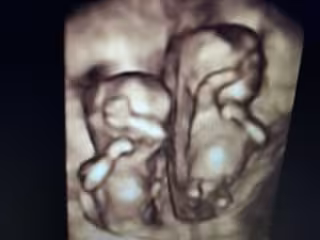

Ecografía de gemelos

El Hospital Universitario de Torrejón de Ardoz (Madrid) está participando en el estudio 'EVENTS' (del inglés 'Early vaginal progesterone for the prevention of spontaneous preterm birth in TwinS), que tiene como objetivo la prevención de partos prematuros en gemelos.

Con el patrocinio de The Fetal Medicine Foundation, en el Hospital de Torrejón se ofrece la posibilidad de participar en el estudio a todas aquellas mujeres con gestaciones gemelares bicoriales o monocoriales (mellizos o gemelos) que acudan al hospital antes de la semana 14 del embarazo.

El objetivo es analizar si, con el uso preventivo de progesterona vaginal desde el primer trimestre de embarazo, se reduce la incidencia de parto antes de la semana 34, periodo en el que la prematuridad asocia peores consecuencias. El estudio comenzó en agosto del 2017 y, hasta la fecha, ya han participado más de 700 madres en España, Bélgica, Bulgaria, Francia, Italia y Reino Unido. Su finalización está prevista para la segunda mitad de 2019, cuando se alcance la cifra total de 1.080 gestaciones.